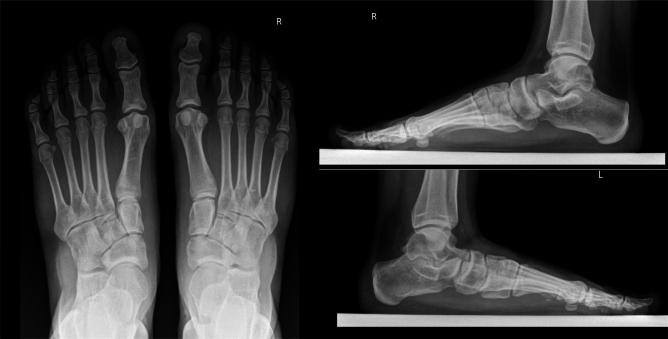

We present our experience with combined hind-foot alignment and medial arch reconstruction by in-situ naviculocuneiform arthrodesis for treatment of flexible flatfoot in children. We retrospectively evaluated clinical data available from pediatric (< 18 years old) patients treated for flexible flatfoot in our department.

At a minimum 24-month follow-up, patients who undergo flat-foot deformity correction using a surgical technique combining sinus tarsi arthroeresis and medial arch reconstruction by naviculocuneiform arthrodesis experience good short-term results.

我们介绍了通过原位舟楔关节融合术进行后足对线和内侧足弓重建联合治疗儿童柔韧性扁平足的经验。我们回顾性评估了在我们科室接受柔韧性扁平足治疗的儿科(<18岁)患者的可用临床数据。

在至少24个月的随访中,采用距下关节制动和舟楔关节融合术进行内侧足弓重建的手术技术矫正扁平足畸形的患者,短期效果良好。